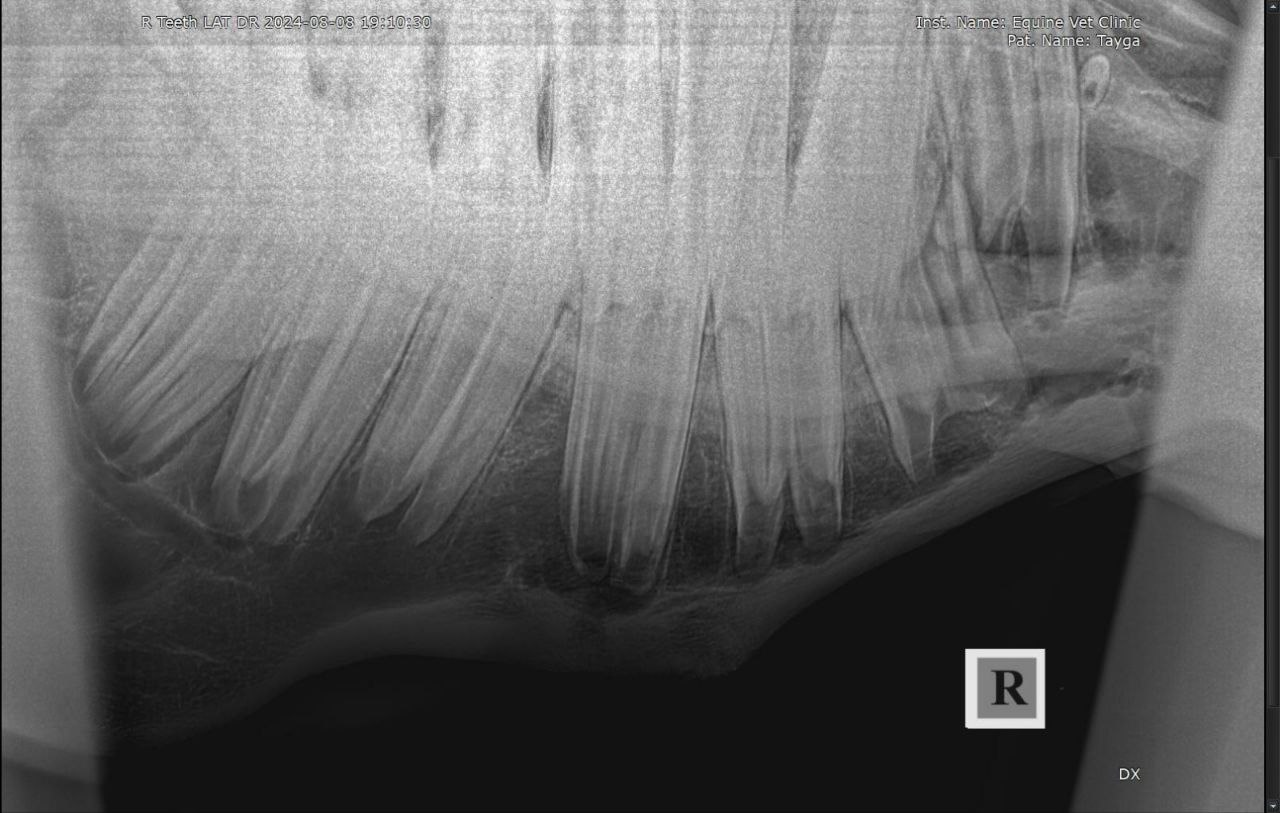

Результаты рентгенологического исследования: наблюдается неравномерная рентгенологическая плотность вокруг верхушки корня и утолщение кортикальной зоны кости нижней челюсти в проекции 408 зуба. Зондированием свища в нижней челюсти установлена вовлеченность корня 408 зуба в формировании канала свища.

Осмотр ротовой полости и зубов: отклонений в целостности и форме 408 зуба не выявлено. Пальпаторно и визуально извне наблюдается утолщение правой ветви нижней челюсти и наличие свища.

Диагноз: апикальный абсцесс 408 зуба с формированием свища нижней челюсти.